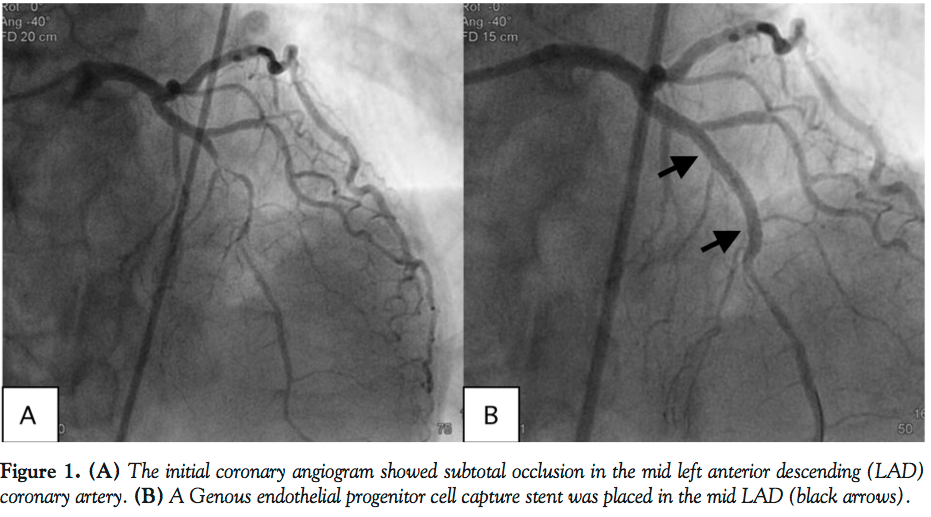

A 78-year-old man was referred for intermittent chest pain during preoperative risk assessment for stomach cancer. Echocardiogram showed anterior wall motion abnormality during chest pain. Coronary angiogram revealed tight stenosis in the mid left anterior descending (LAD) coronary artery (Figure 1A). In anticipation of the urgent surgery and chest pain due to unstable angina, plain old balloon angioplasty (POBA) was applied to the stenotic lesion. However, there was still significant residual stenosis and minor dissection was

suspected after POBA. It seemed that the deployment of a stent was inevitable. An endothelial progenitor cell (EPC) capture stent (Genous; Orbus Neich Medical Technology) was implanted (Figure 1B) to promote reendothelialization by CD 34 antibodies attached to stent struts. The patient was started on dual antiplatelet therapy after the procedure. Two weeks later, the patient underwent repeat coronary angiography and optical coherence tomography (OCT). There was no in-stent restenosis; however, two newly developed small aneurysms were found behind the stent struts (Figure 2). All stent struts were covered on OCT.